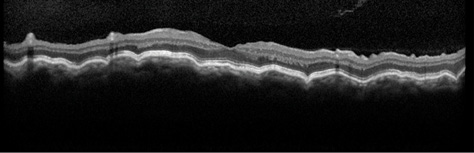

On the first postoperative day, the patient's visual acuity was 20/80, and the IOP was 14 mm Hg OS. By 1 month after the open bleb revision, the IOP had stabilized at 13 mm Hg OS, and the patient's visual acuity had improved to 20/25 OS. A slit-lamp examination was notable for a low-lying diffuse bleb without evidence of a wound leak. A fundus examination and OCT confirmed significant improvement in the patient's chorioretinal folds that was consistent with the reversal of hypotony maculopathy (Figure 2).

Figure 2. An OCT image of the patient's left eye after the second bleb revision shows significant improvement in the previously noted chorioretinal folds. Visual acuity is 20/25, and the IOP measures 13 mm Hg.